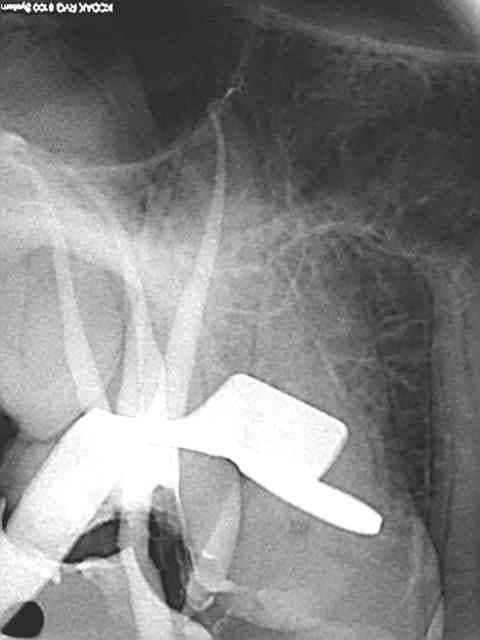

R29 uvltlt - Eugenol

R49 enunsh - Eugenol

R22 vkd0tr - Eugenol

R23 pmkimv - Eugenol

R26 gr1kkt - Eugenol

R34 w9wpow - Eugenol

Img 0052 dkvbyu - Eugenol

Leandro

28/02/2013 à 21h54

Joli travail!